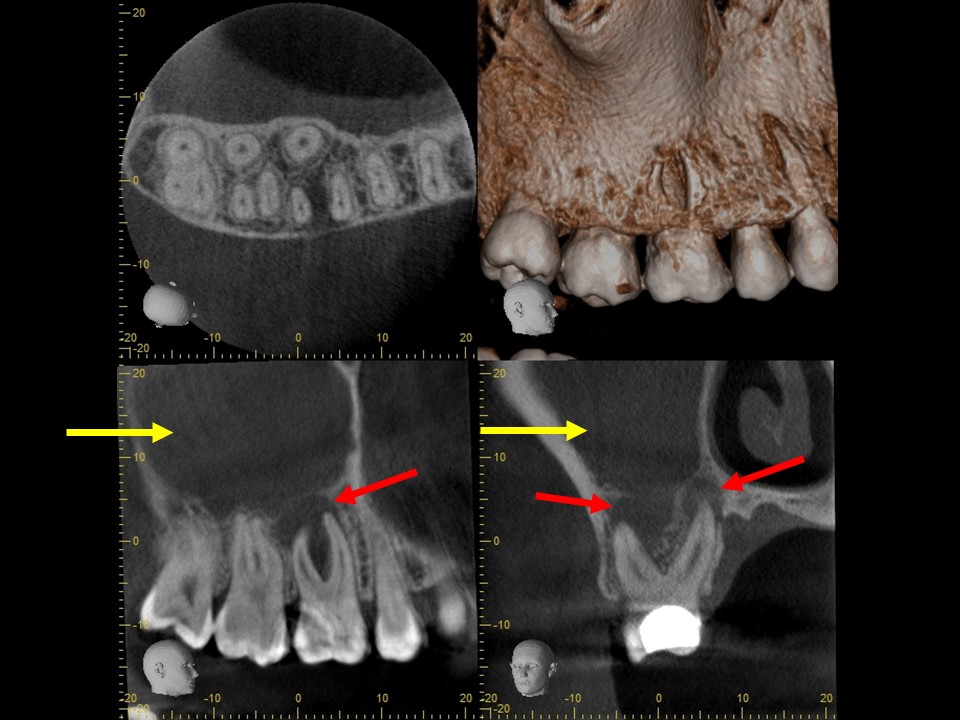

治療前レントゲン | 治療前CT |

---|---|

治療前レントゲン |

---|

治療前CT |

治療前のレントゲンおよびCT画像です。右上6番には歯髄に達する大きなコンポジットレジン充填がされています。

根尖部の骨は黒く大きく溶け(赤矢印)、ほぼ上顎洞と交通しています。

上顎洞内部は上方までX線不透過性が亢進し(白くなっています)、典型的な上顎洞炎の像を呈しています(黄矢印)。

根管充填後のレントゲン画像です。根尖部までしっかりとお薬が詰まっているのが分かります。根尖病変および歯性上顎洞炎の予後を確認するため3か月ほど経過観察を行います。

根管充填3か月後のCT画像にて、根尖病変および歯性上顎洞炎の予後を確認しました。根尖病変は顕著に縮小して骨の再生が見られ、上顎洞炎はほぼ治癒していました(下写真)。

根管治療14か月後のレントゲン及びCT画像では、根尖部のX線透過像および上顎洞内の不透過像は完全に消失しているのが分かります(下写真)。根尖部の骨の再生と上顎洞の正常化が認められ、根尖病変ならびに歯性上顎洞炎は完全に治癒しました。

根管充填3か月後のCT画像です。根尖病巣は顕著に縮小しており、骨の再生を認めます(赤矢印)。上顎洞の炎症も消退し、ほぼ正常像を呈していることが分かります(黄矢印)。病状が治癒傾向を認めるため、歯冠修復処置を行っていきます。

根管治療14か月後のレントゲンおよびCT画像です。術前にあった根尖部のX線透過像(赤矢印)ならびに上顎洞内のX線不透過性の亢進(黄矢印)は完全に消失し、根尖病変および歯性上顎洞炎は良好に治癒しているのが確認できます。